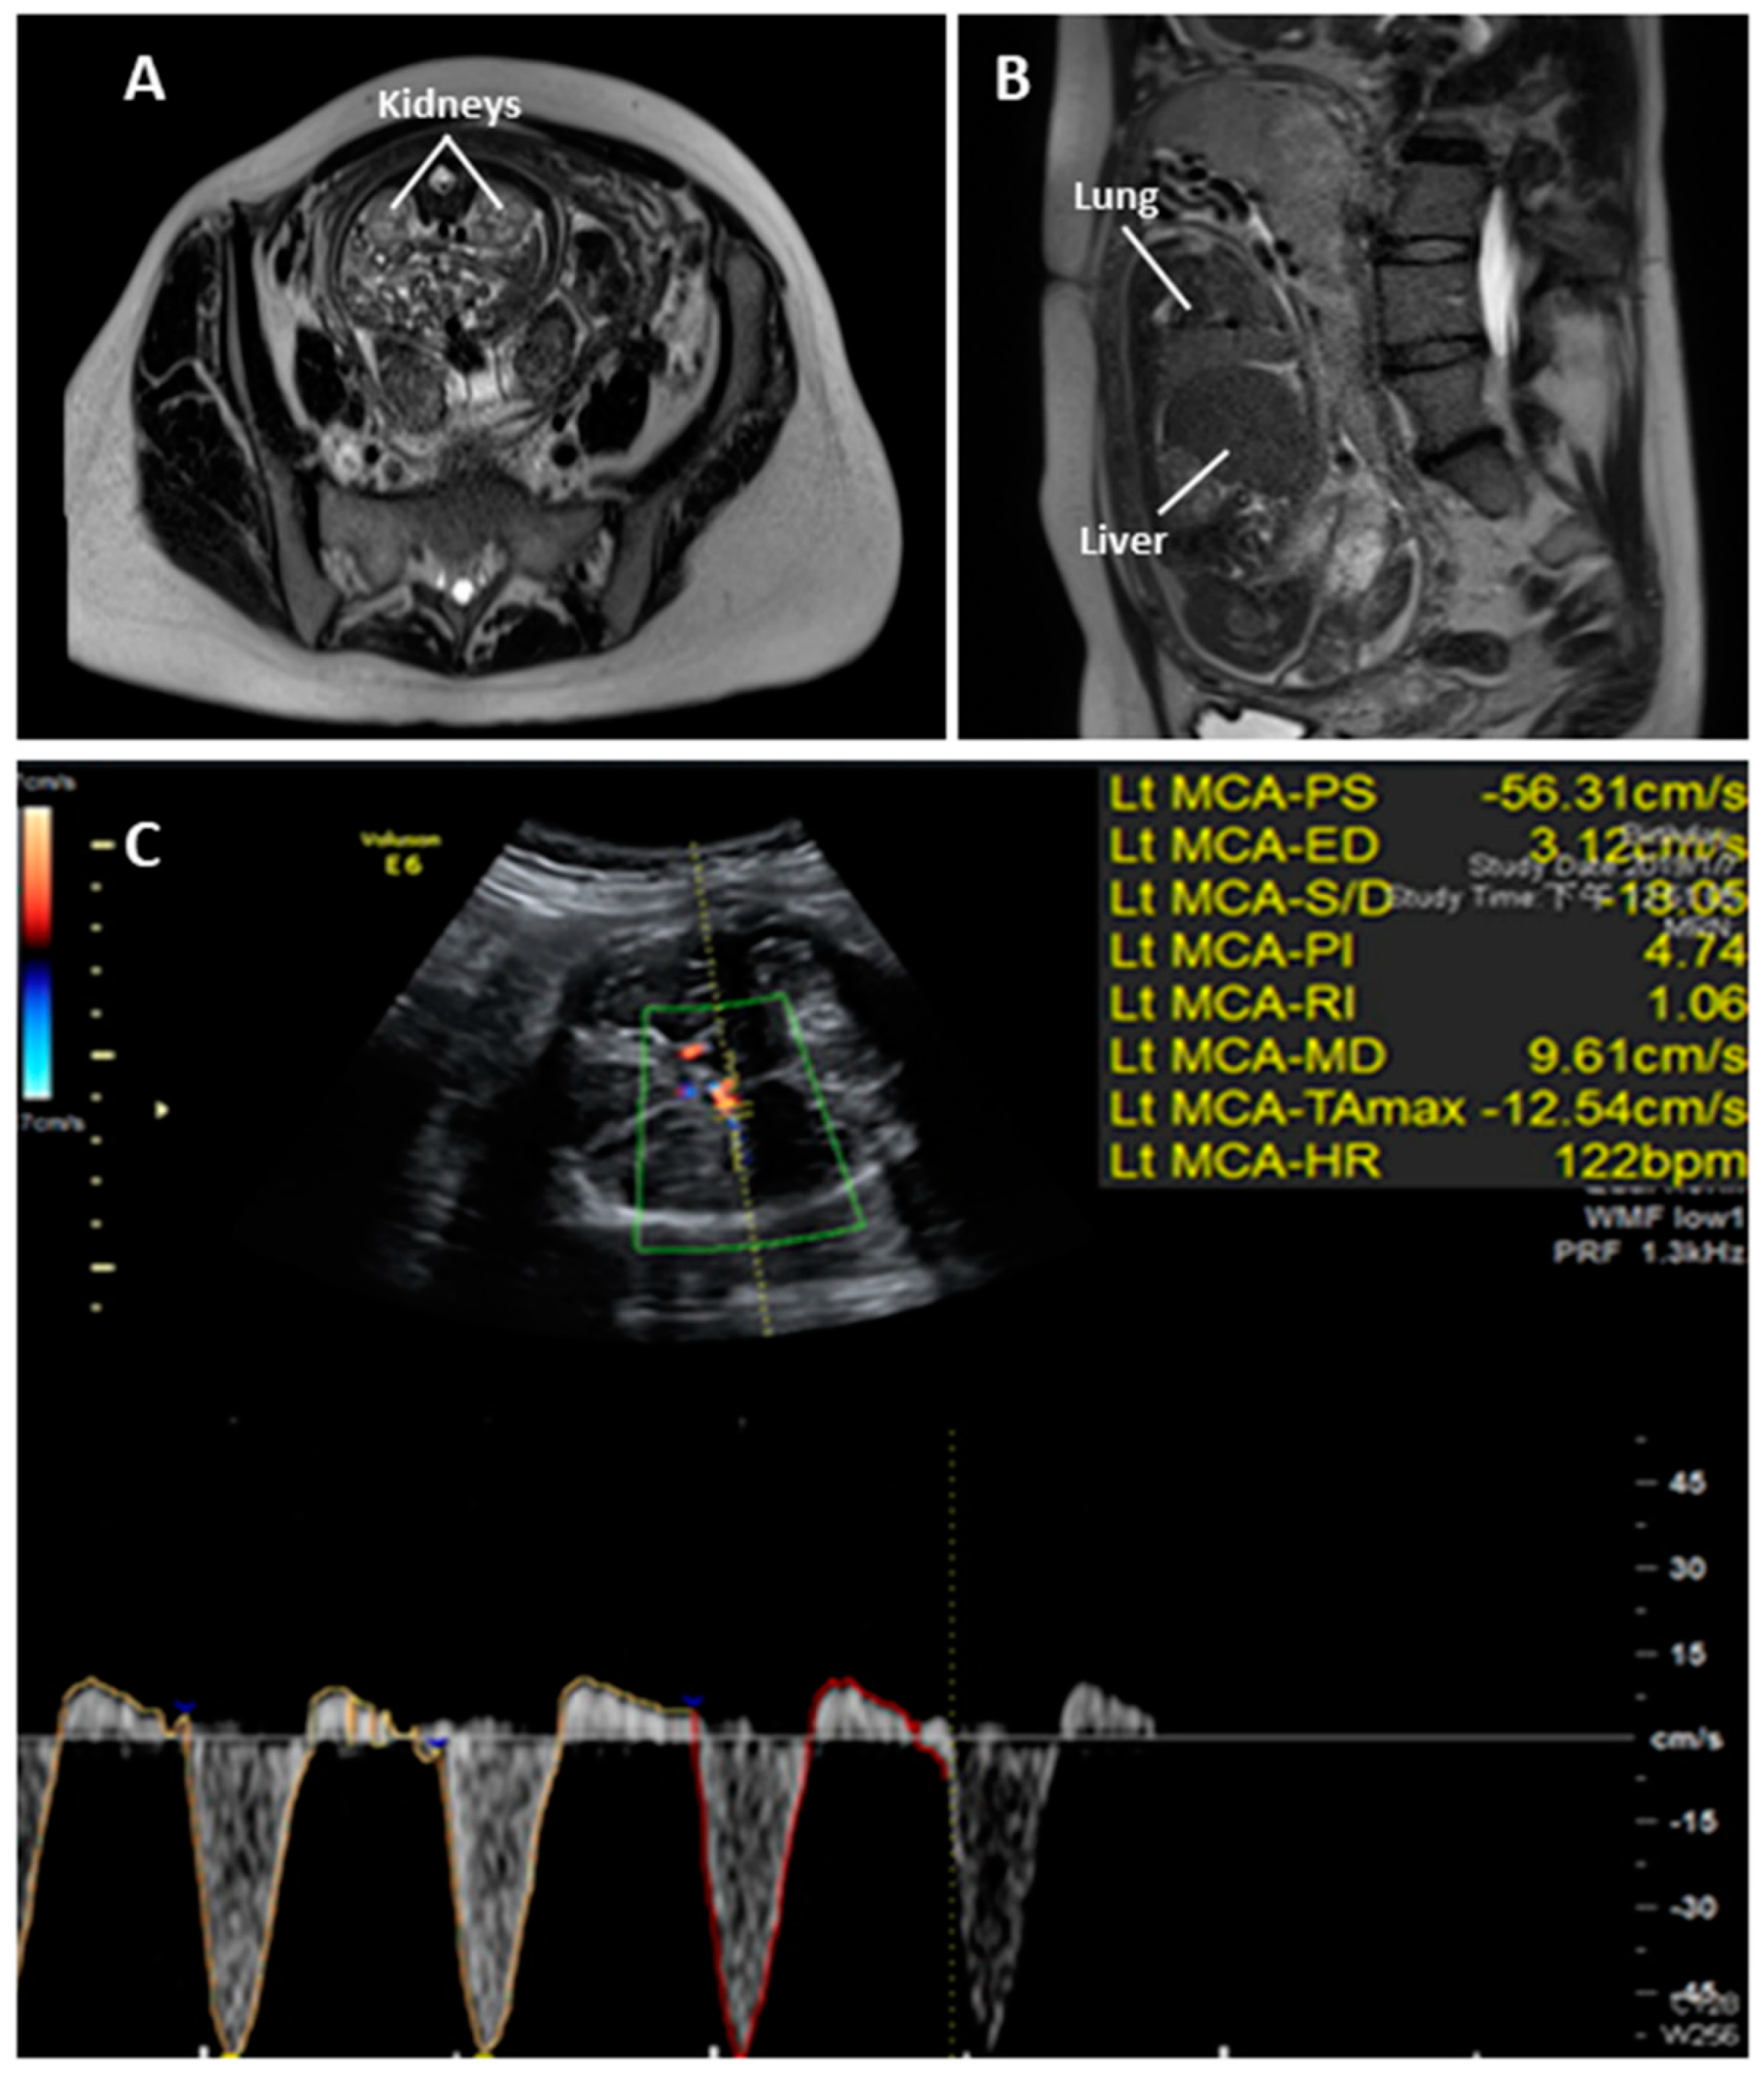

2. Case Report